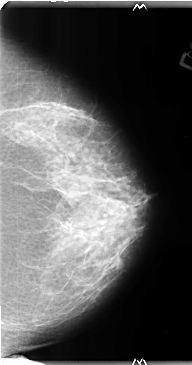

B_3134_1.RIGHT_MLO

LEFT_MLO LINES 4696 PIXELS_PER_LINE 2728 BITS_PER_PIXEL 12 RESOLUTION 50 NON_OVERLAY

FILE: B_3134_1.RIGHT_MLO.OVERLAY

TOTAL_ABNORMALITIES 1

ABNORMALITY 1

LESION_TYPE CALCIFICATION TYPE PLEOMORPHIC DISTRIBUTION CLUSTERED-LINEAR

LESION_TYPE MASS SHAPE IRREGULAR-ARCHITECTURAL_DISTORTION MARGINS SPICULATED

ASSESSMENT 5

SUBTLETY 4

PATHOLOGY MALIGNANT